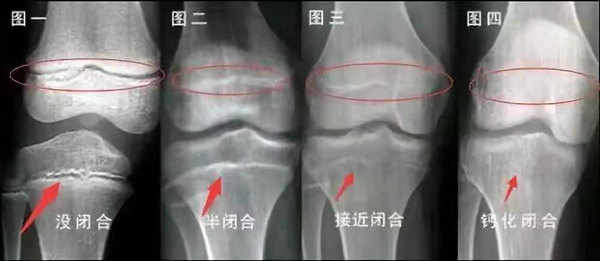

我們都知道,人體的高矮是由骨骼的生長(zhǎng)發(fā)育決定的,特別是下肢長(zhǎng)骨。長(zhǎng)骨呈長(zhǎng)管狀,在長(zhǎng)骨的兩端有一種專管骨骼生長(zhǎng)的骺軟骨,它與干骺端之間有一盤狀軟骨結(jié)構(gòu)稱為骺板(線),在幼兒的X光片上表現(xiàn)為一條較寬的透光帶。 (見下圖)

未成年時(shí)隨著年齡的增加骺軟骨端不斷骨化,骨骼就不斷增長(zhǎng)。當(dāng)骨骺線完全閉合時(shí)骨骼就停止生長(zhǎng),個(gè)子也就不再增長(zhǎng)了。一般骨骺端完全閉合的年齡是18~20歲左右。